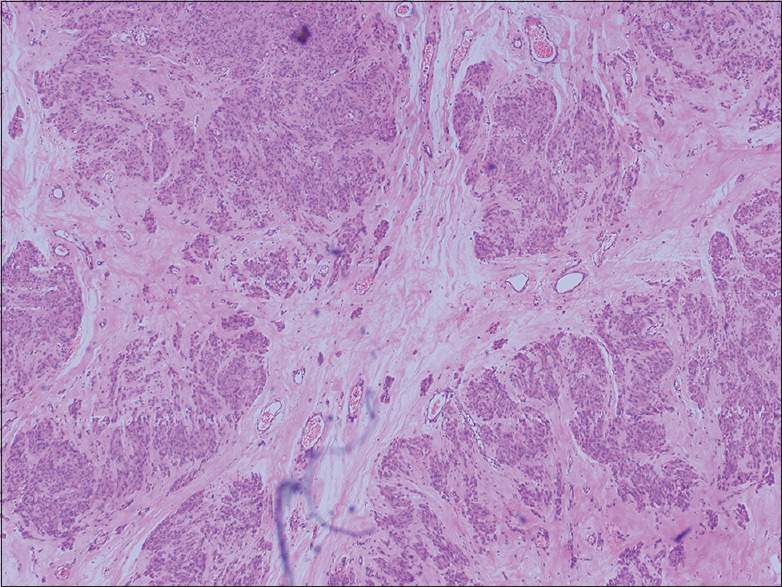

Leiomyomas are benign smooth muscle tumor of the uterus with varied morphology that are well known to undergo secondary changes. A variety of other unusual patterns of uterine leiomyoma have been described, such as parasitic leiomyoma, cellular leiomyoma, symplastic or bizarre leiomyoma, epithelioid leiomyoma, intravenous leiomyomatosis, and leiomyoma with secondary changes. Some cotyledonoid dissecting leiomyoma (CDL) appears as large fungating masses with widespread extension into the broad ligament and pelvic cavity. Due to its rarity and a clinician's lack of familiarity, such tumors are sometimes misdiagnosed as malignancies. We present a rare case report of CDL. It is a diagnostic challenge for clinicians, pathologists, and radiologists and can be confused with malignancy due to its large size. After extensive literature research, we found 28 case reports of this variant. Little is known in the literature about this entity. We present here a case report of a 65-year-old female emphasizing its clinical, radiological, gross, and microscopic findings. A total hysterectomy was performed on the patient. This tumor does not have malignant potential, but clinicians and pathologists must be aware of its existence to avoid over-treating patients as malignancy.